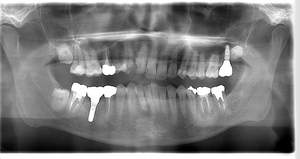

レントゲン写真

- Befor

- After

| 年齢 | 50代・男性 |

|---|---|

| 主訴 | 左上7番 左下5番7番 |

| 治療内容 | ・インプラント埋入 ※1:GBR(骨造成)・・・骨再生誘導法。骨の高さや厚みを人工骨や人工膜などを使用し再生する方法 |

| 治療費 | 合計:1,809,500円(税込) ■内訳 ・左上7番 ・左下5番7番 |

| 治療期間 | 左上7番約1年 左下5番7番約10ヵ月 |

| 治療方針 | 左上7番は昔他院で被せものをしており、被せものの中が歯ぐきの中まで虫歯になっていたため抜歯せざるを得ない状態だった。抜歯と同時に骨造成を行い、骨が出来るまで4ヵ月待ってからインプラントを埋入した。 ※2ポンティック・・・歯のない部分を補うダミーの歯。 |

| 担当者所見 | 元々金属の被せものが多く入っていたため、2次カリエス※3が多かった。今回は金属ではなく、ジルコニアを使用し、2次カリエスにならないよう、患者様にはブラッシング指導とメンテナンスの重要性をお伝えした。 ※3二次カリエス・・・詰め物や被せものを入れた歯が虫歯になること。 |